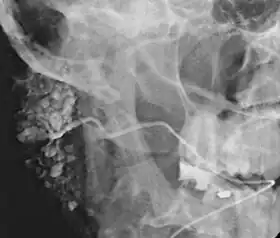

|  Sialogram in a patient suspected of Sjögren's syndrome | |

Sialography (also termed radiosialography) is the radiographic examination of the salivary glands. It usually involves the injection of a small amount of contrast medium into the salivary duct of a single gland, followed by routine X-ray projections.[1]

The resulting image is called a sialogram.

This procedure is indicated when there is recurrent swelling and pain on the face but ultrasound has not revealed any problems. If Sjögren syndrome (also known as Sicca syndrome, an autoimmune disease that affects the lacrimal and salivary glands, causing reduced tears and saliva production) is suspected, this procedure is useful. Besides, when interventional proecudre is planned such as stone removal from salivary ducts or dilatation of the strictures in the salivary gland, this procedure is also indicated.[4] However, for those who are pregnant, with allergy to iodinated contrast, and ongoing infection or inflammation of the face, the procedure is contraindicated.[4]

This study is interpreted by evaluating the morphology of the salivary ducts for obstructions and chronic inflammation. Sialodochitis is a term describing dilation of the ducts caused by repeated inflammatory or infective processes. There is also irregular salivary duct stricture (narrowing) of the duct, which creates an appearance known as "sausage link" pattern on a sialogram. Suggestions of abscesses and autoimmune diseases such as Sjögren syndrome can also be elicited. Sialadenitis is inflammation of the salivary glands, which may cause acinar atrophy and create an appearance known as "pruning of the tree" on a sialogram, where there are less branches visible from the duct system. A space occupying lesion that occurs within or adjacent to a salivary gland can displace the normal anatomy of the gland. This may create an appearance known as "ball in hand" on an sialogram, where the ducts are curved around the mass of the lesion.[6]